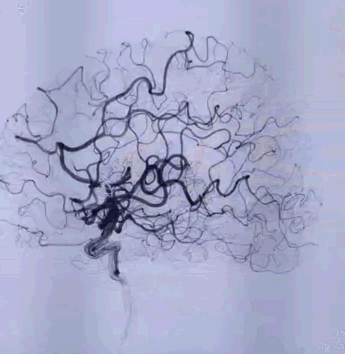

Tubridge Case 2